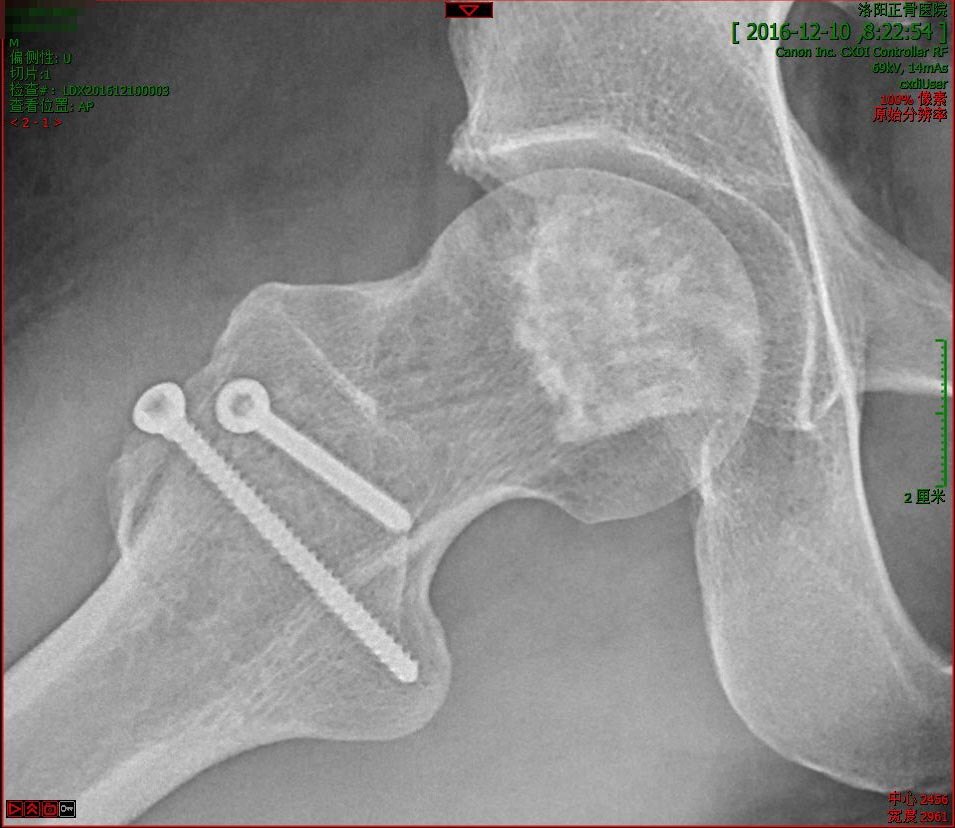

股骨頭壞死早中期經(jīng)常面臨兩個問題:一、容易誤診、漏診,以至于失治誤治;二、治療方法選擇困難,對手術(shù)與否、何時手術(shù)心存疑慮,甚至錯過最佳治療時機。希望本案例可提供一點借鑒。男性,41歲,2016年12月主訴“不明原因右臀部疼痛”以雙側(cè)股骨頭壞死為診斷住院治療。在當?shù)蒯t(yī)院磁共振檢查確診,左側(cè)壞死尚無癥狀。在我院CT檢查示:X線檢查:術(shù)中所見:我們采用外科脫位技術(shù),充分暴露股骨頭,經(jīng)圓韌帶窩窗口挖出死骨并進行植骨。術(shù)中見關(guān)節(jié)面軟骨發(fā)生退變,死骨松軟如豆腐渣。術(shù)后復(fù)查:術(shù)后1年復(fù)查:術(shù)后3.5年復(fù)查:骨吸收是股骨頭壞死修復(fù)過程中非常棘手的問題,必須采取積極措施阻止進一步惡化。通常會采取多種方法,包括藥物治療、高能聚焦沖擊波治療等。半年后再次復(fù)查:又過了1年,術(shù)后第5年復(fù)查:術(shù)后7年復(fù)查:術(shù)后8年復(fù)查:至于左側(cè)股骨頭壞死,因為面積較小,簡單采用中藥、沖擊波治療,一直情況穩(wěn)定,這次就不展開贅述。如下:幾句話總結(jié)1.年輕股骨頭壞死保頭要趁早,切莫沉醉在所謂“秘方”的幻想中,建議通過全面檢查評估制定周全的治療方案;2.大約2/5的早中期病例可通過保守治療控制病情,但需要手術(shù)的情況也不能視而不見,理性、客觀對待病情;3.股骨頭壞死的病情轉(zhuǎn)歸十分復(fù)雜,別人成功的經(jīng)驗一定不是放之四海而皆準,除了因人而異進行治療之外,必須堅持定期復(fù)查、長期觀察,以準確掌握病情變化,在關(guān)鍵節(jié)點調(diào)整治療措施;4.任何一種單一治療措施發(fā)揮的作用總是有限的,就如做飯放調(diào)料,某一種佐料看似不起眼,缺一樣就少一種味道,和諧搭配才能取得最佳效果。同樣,藥物治療、物理治療,甚或手術(shù)治療需要有機結(jié)合,切莫盲目相信某一種方法的“神奇”效果。